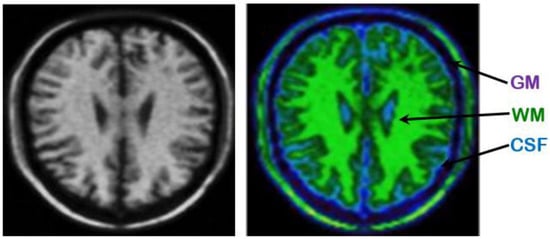

An example presented in Figure 4, illustrating an anatomical image labeled WM, GM and CSF, resulting from automatic segmentation based on the proposed hybrid approach. The brain tissues in the calculated image are labeled WM (green color), GM (purple color) and CSF (blue color), where the tissue volumes are well defined and classes are clearly legible, with a clearer anatomical localization that allows localization of basal ganglia and cortex (GM), fissures and ventricles (CSF) and WM tissue.